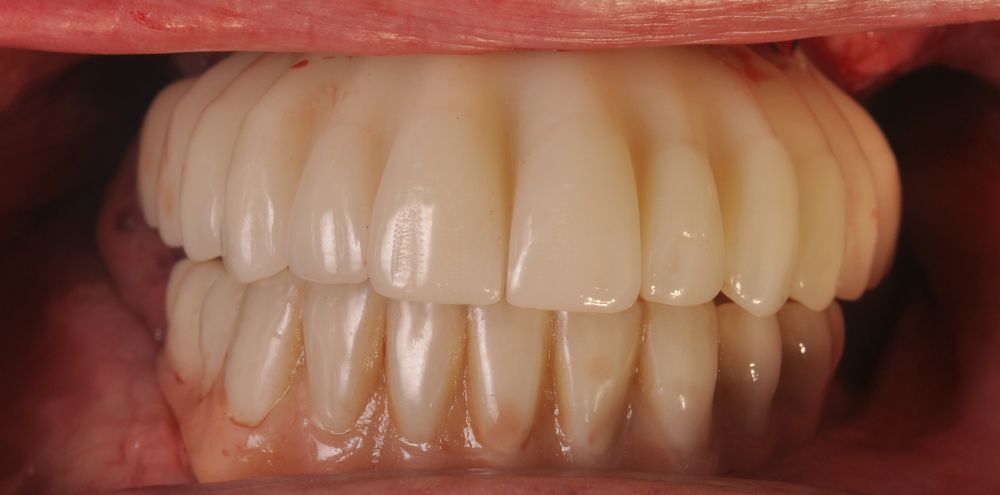

Two months later, with the soft tissues healed around the connections (Figure 16), a new intraoral scanning was made of the implants and the provisional prosthesis for future restoration. A FRI type passivity test (rigid impression splint) was manufactured with an aluminium structure to assess the correct fit on the implants (Figure 17). For implant-supported rehabilitation, a sintered structure was made in chrome-cobalt with machined bases covered with acrylic resin teeth from Bredent® (Figures 18-21).

The patient has been checked every six months this year, performing X-rays and cleaning the structure, without finding any prosthetic or periodontal complications.